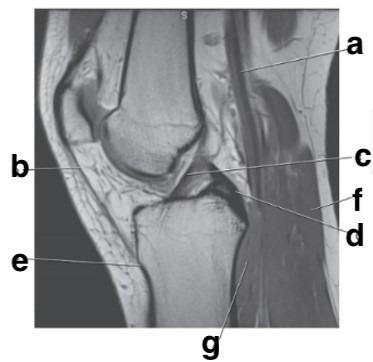

Supraspinatus tendon

Supraspinatus muscle

Which letter is pointing to the posterior cruciate ligament?

e

Achilles tendon

Which letter is pointing to the patellar ligament?

b